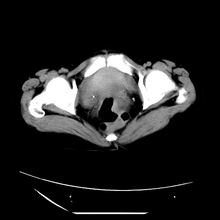

肾窦脂肪瘤病及肾替代性脂肪瘤病被认为是脂肪增殖程度不同的一种疾病。正常情况下肾窦内有少量脂肪组织充填,在某种情况下肾实质会发生萎缩,而以肾窦、肾门为中心脂肪或(和)纤维组织可出现增殖,当增殖局限在肾窦、肾门区时称为肾窦脂肪瘤,若同时部分或全部取代了萎缩破坏的肾实质时称为肾替代性脂肪瘤病。

发病机理有2种学说,大部分人认为是由于某些具有破坏性的肾脏疾病,如肾结石并感染、肾结核等造成肾破坏、萎缩,继发了大量的脂肪组织增殖;另一部分则认为肾脏慢性炎症可刺激脂肪组织的增殖,肾萎缩是继发的。

ct典型表现为以肾窦肾门为中心大量弥漫性脂肪积聚,鹿角状结石及萎缩的肾实质。合并肾周感染时,肾轮廓不清,周围有粘连性改变。

诊断主要需与含脂肪的肾肿瘤加以区别,如血管平滑肌脂肪瘤、脂肪肉瘤、脂肪瘤